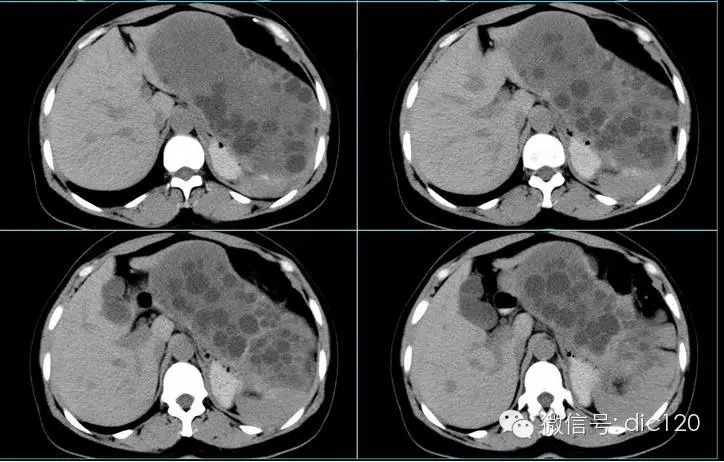

肝脏、脾脏、腹腔包虫病一例

简要病史:患者于入院前19年因诊“卵巢囊肿”行手术治疗,术中诊断为包虫病,术中囊液污染腹腔。术后患者恢复良好。患者于3年前无意中发现左上腹部出现一包块,约3*3cm大小,无触痛,活动度可,无发热、乏力,无恶心、呕吐,无腹痛、腹泻,无胸闷、气短,无皮疹等不适,查B超考虑肝包虫(多发)、脾肾间隙处实性占位,考虑包虫。

肝包虫病CT表现:

(1)肝内圆形或类圆形低密度区,CT值可在-14~25HU,密度均匀一致,增强后无强化表现。边界清楚,光整。囊壁及囊内分隔有增强效应。

(2)大的囊腔内可见分房结构或子囊(囊内囊)。子囊的数目和大小不一。如子囊主要分布在母囊的周边部分呈车轮状。